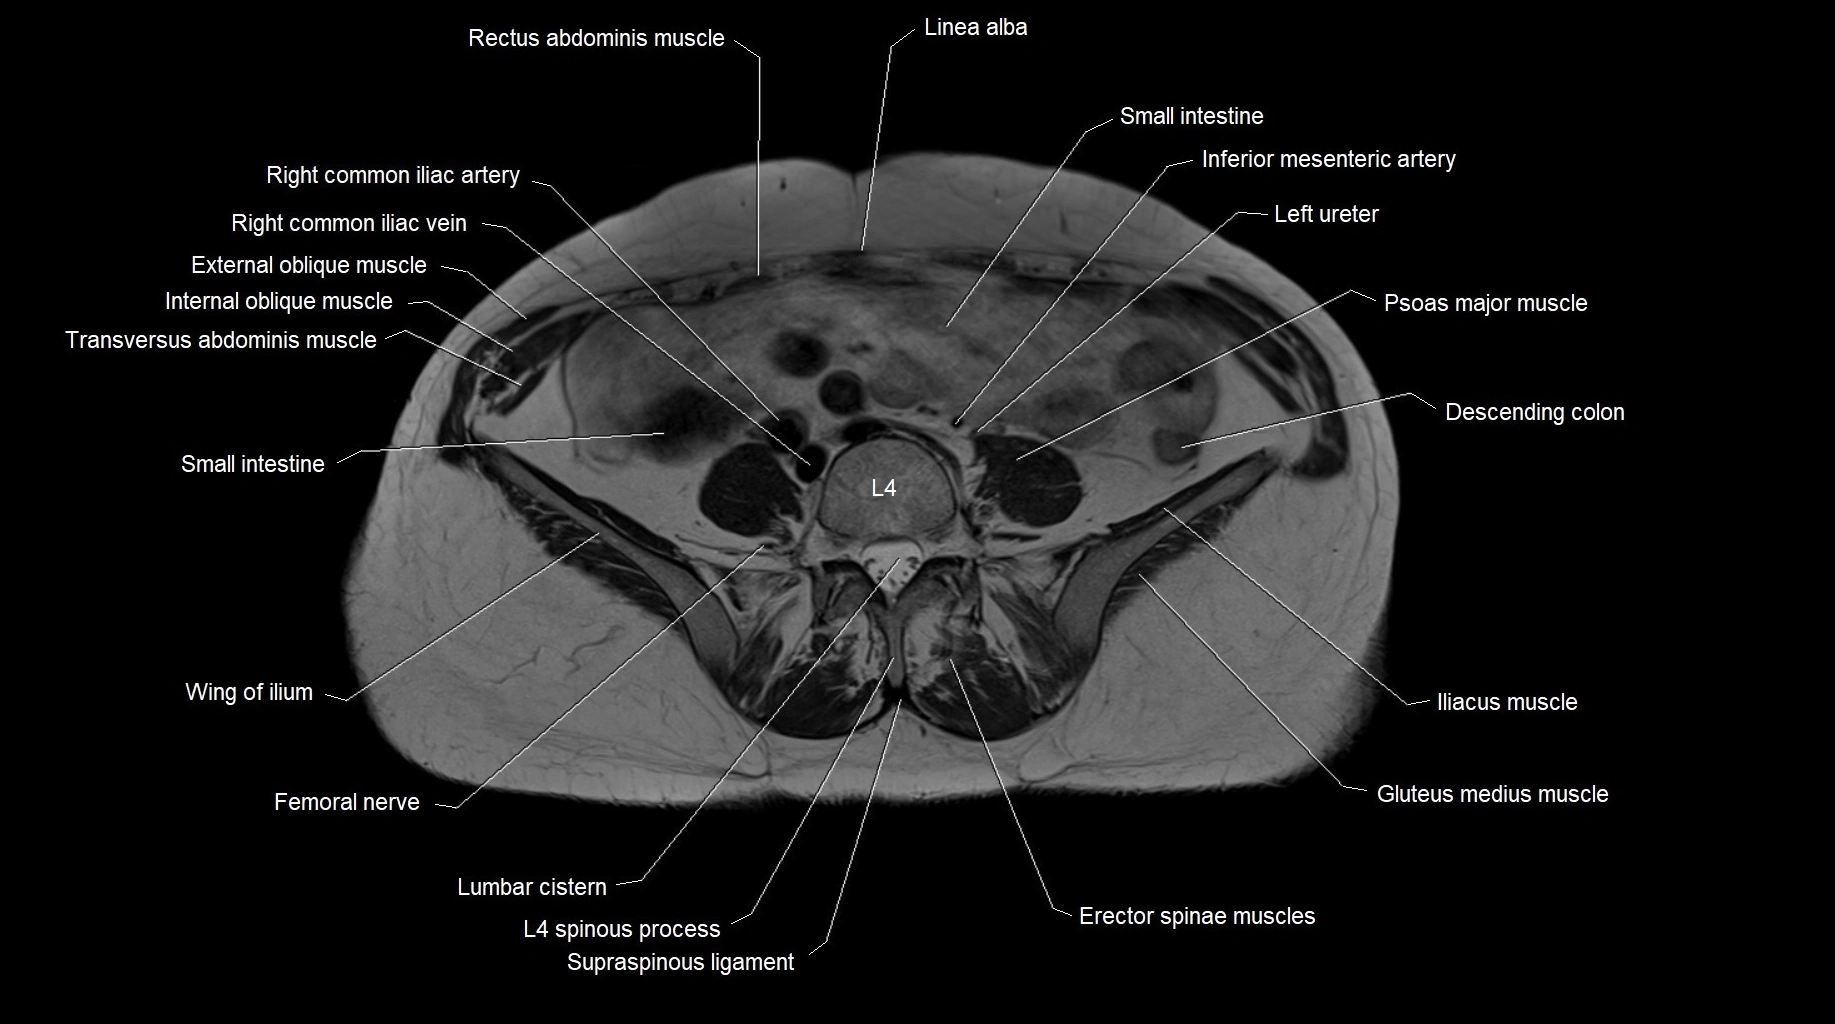

MRI images